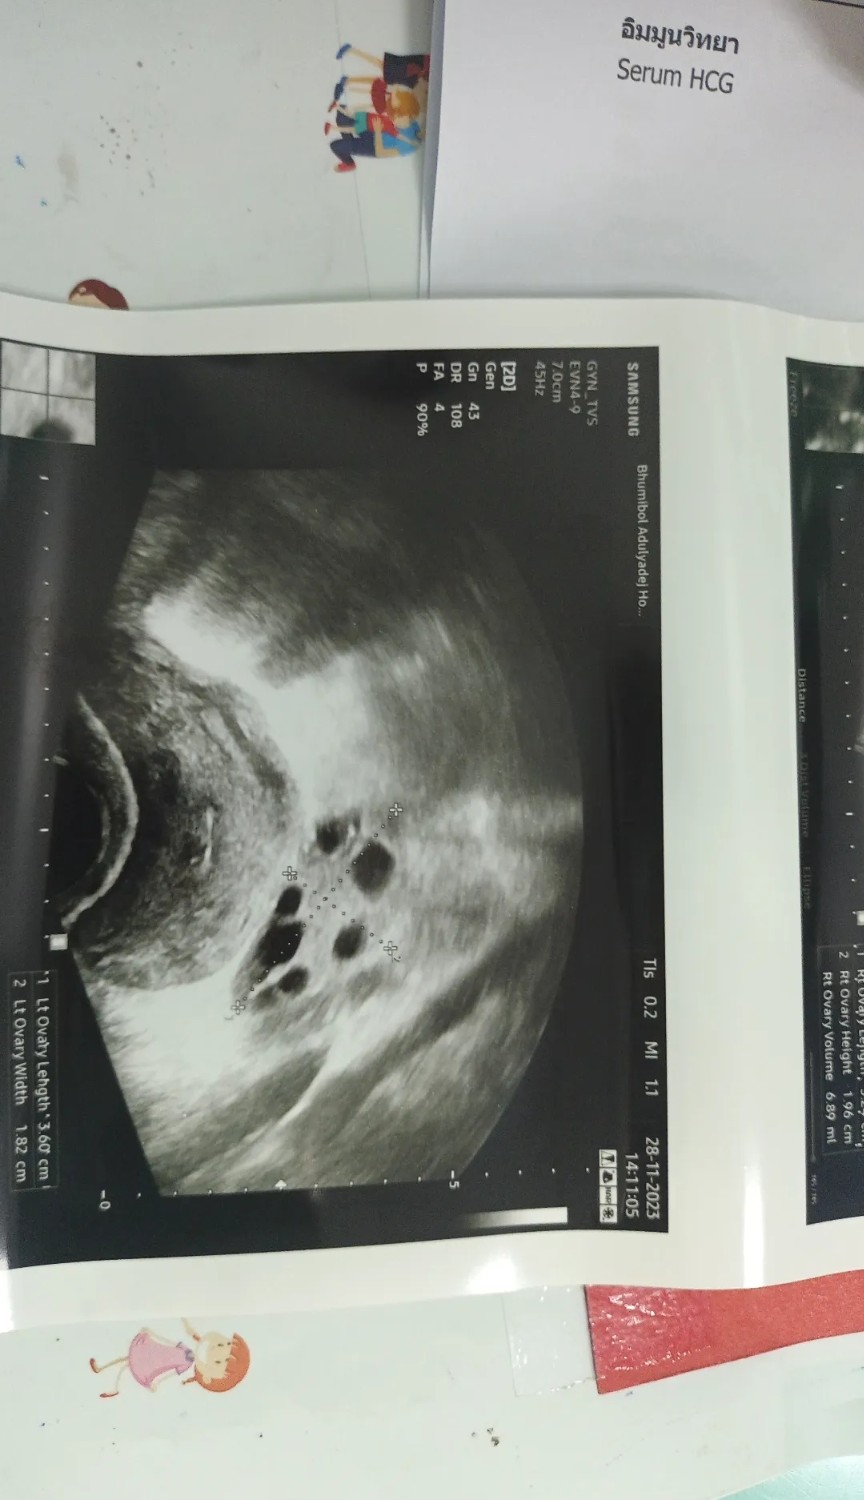

อยากทราบว่ารูปนี้ท้องกี่เดือนคะ